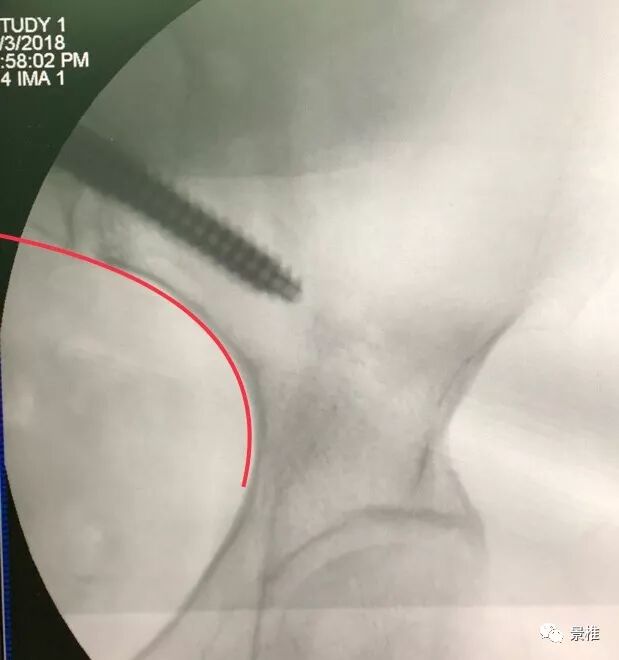

这个技术虽然比较好掌握,但还是会误穿出去(brench),有损伤血管的风险。因此在学习早期,钉道制备过程中务必透视定位。

术中C臂头尾侧倾斜20°-30°,左右斜45°透视,确保钉道在泪滴内。注意示意图中球管的位置,不要摆反了。辐射量也小一些 骨科手术C臂透视防护指南

正位片透视钉道在坐骨切迹上方。